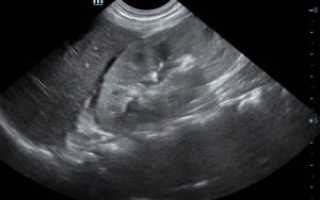

Фото МРТ надпочечников

Андростерому можно диагностировать, основываясь на клинических проявлениях, а также на результатах лабораторных и инструментальных исследований. Эти методы не только подтверждают предварительный диагноз, но и помогают отличить заболевание от других патологий, которые также могут вызывать вирилизацию. Для этого применяются следующие методы:

- РКТ. Этот способ визуализации помогает четко увидеть андростерому, чаще всего опухоли обнаруживаются в одном из надпочечников.